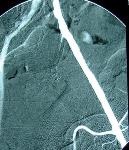

Perkutánní transluminální angioplastika (PTA) + zavedení stentu pánve a dolních končetin

PTA se provádí v místním znecitlivění a je to výkon nebolestivý. Do tepny obvykle v třísle se zavede jehla, přes kterou zavedeme vodič a kterým pronikneme skrz postiženou oblast až do „zdravé“ tepny. Poté do postižené oblasti zavedeme speciální balonkový dilatační katetr (balónek) a „nemocnou“ tepnu ošetříme buď pouze roztažením balonku nebo zavedením stentu, který drží požadovaný průměr ošetřované tepny. Současně se získávají snímky léčené oblasti před a po léčbě pomocí PTA. Na konci výkonu lékař odstraní zaváděcí pouzdro, balonek a vodič (instrumentárium) a místo, kudy bylo instrumentárium zavedeno se stlačí na dobu nezbytně nutnou k zástavě krvácení z tepny. Délka výkonu je zcela individuální v závislosti na lokalizaci a závažnosti postižení tepenného systému. Délku výkonu upřesní výkon provádějící intervenční radiolog.